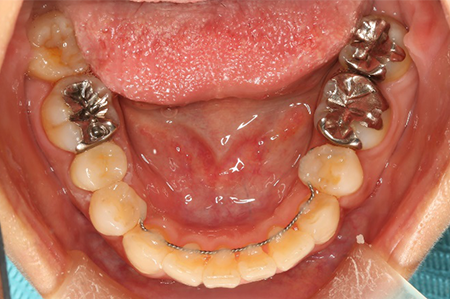

下の口腔内写真は初診時と矯正治療+補綴治療後のものになります。

矯正治療と言っても、成人で虫歯の治療などが多数歯に渡って既に施されている場合、被せ物を変えていく必要があるのか、虫歯はないか、抜歯をする必要があるか、考えないといけないことがたくさんあります。

一般的な矯正歯科ではできない審美治療など、矯正後のその先まで考えて治療計画を立案し治療を行っていくことが出来ます。

虫歯が大きかった右上の奥歯も残すことが出来ました。

連結してあった前歯の被せ物(歯茎まで黒くなっている)も矯正後にきれいに治療することが出来ています。

歯並びが悪いと見た目が悪いだけではなく歯磨きがしづらく、噛み合わせが悪いことで力のかかり方が不均一になってしまい歯に亀裂が入り虫歯になりやすくもなります。

当院ではトータルで口腔内を診ることに重きをおいて診療しています。

1本1本の歯にはそれぞれ役割があり、矯正治療を行うことでそれぞれの歯に適正な咬合力がいき渡るようにすることが出来、虫歯や歯周病になりづらい口腔内に、さらに審美的にもなります。